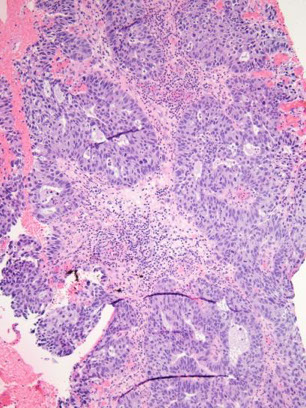

Microglandular hyperplasia

common, mostly in women of reproductive age (assoc c progesterone [OCPs and preg]), and up to 1/20 postmenopausal

- can grossly look like an erosion, polyp or friable raised area on the cervix

- may favor adenocarcinoma if large amt of tissue in bx (ie 3 blocks), lack of subnucleolar vacuoles, transition to other forms of endometrial adenoca, assoc c foamy stromal cells and + vimentin in cytoplasm

Micro: closely packed glands c variable shape and size c acute and chronic inflam c little intervening stroma, giving it a cribriform appearance

- epithelial lining is cuboidal to columnar c uniform nuclei c focal atypia, rare mits and produces mucin pools, possibly signet rings

- no nucleoli, can have different degrees of sq metaplasia

IHC: (+) p63 in reserve cell component, mucin

- neg: cytoplasmic vimentin (vs adenoca), p16 (though can be strongly but patchy positive, in which case doesn't co-localize MIB or cyclin E and not assoc c HPV infx), CD10

- CEA not helpful (neg in adenoca and microglandular hyperplasia)